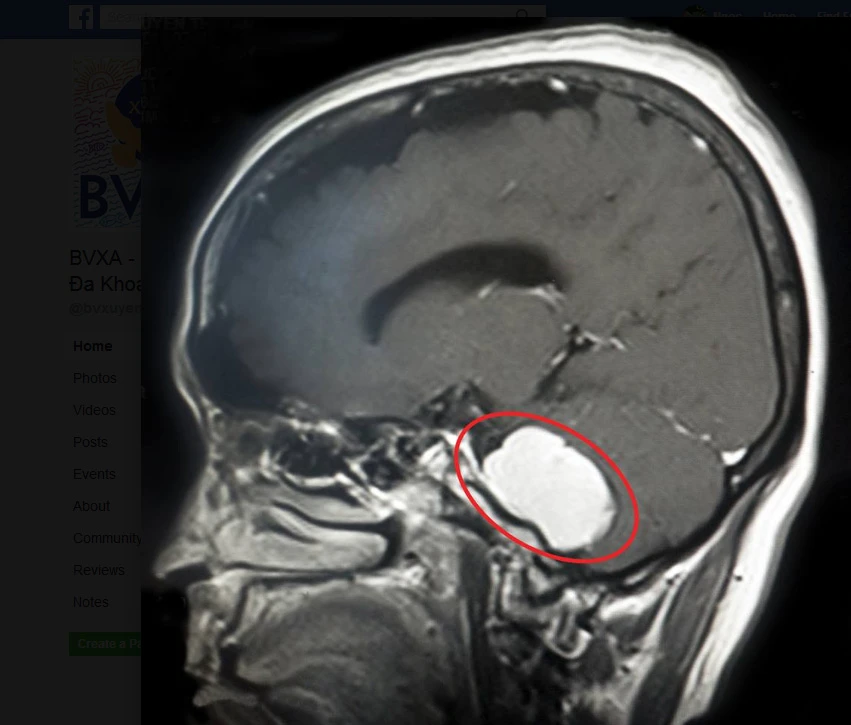

Trước đó, bệnh nhân tới BV Đa khoa Xuyên Á trong tình trạng chóng mặt, hoa mắt, khó thở. Chưa hết, gương mặt bệnh nhân còn bị méo xệch. Kết quả chẩn đoán của các bác sĩ (BS) chuyên khoa Ngoại thần kinh ghi nhận bệnh nhân có khối u não nằm rất sâu ở vị trí liên quan tới nhiều dây thần kinh sọ não và là vùng chức năng quan trọng của não bởi nơi đây điều hành nhịp tim và hô hấp.

Khối u não của bệnh nhân nằm ở vị trí phức tạp. Ảnh: LÊ PHỤNG